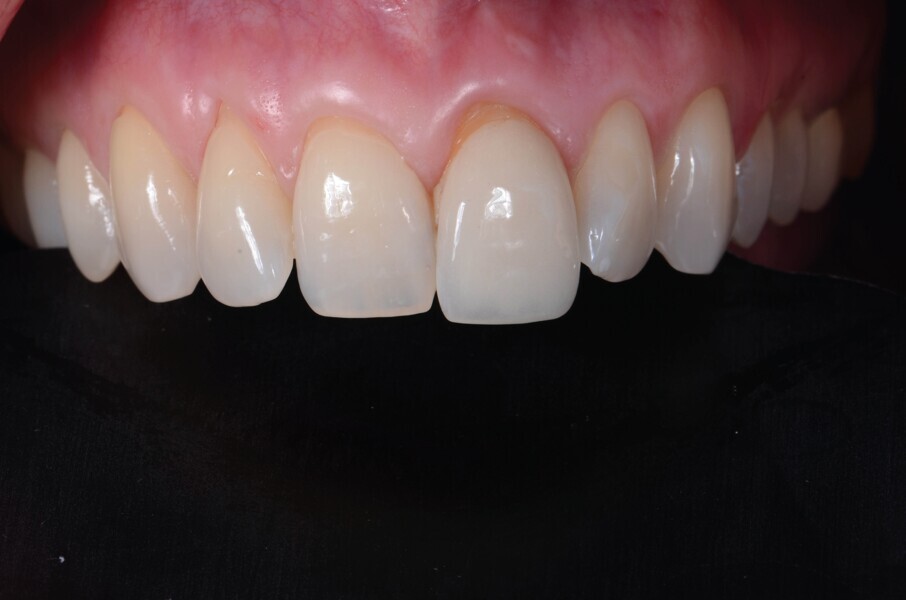

Fig. 20a : Couronne définitive implanto-portée, vue extraorale ;

Fig. 20b : Couronne définitive implanto-portée, vue occlusale.

Le transfert est donc mis en place en bouche (Fig. 18), et une empreinte est prise en technique pick-up, avec un porte-empreinte à ciel ouvert (Fig. 19). La couronne provisoire est remise en place rapidement, afin de prévenir toute rétraction des tissus mous. La couronne définitive en disilicate de lithium est ensuite mise en place (Fig. 20), et est vissée avec couple de serrage de 20 Ncm, conformément aux recommandations du fabricant.

Lors du suivi a cinq ans, on ne peut que constater le résultat esthétique maintenu (Fig. 21). La radiographie montre un niveau osseux stable et une connexion étroite entre l’implant et le pilier (Fig. 22).